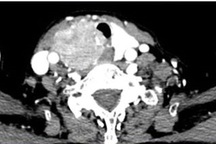

Bệnh nhân là ông P.V.N, 56 tuổi, trú tại Ba Vì, Hà Nội được chẩn đoán bị u giáp thùy trái kích thước 10x6mm. Bệnh nhân được chỉ định phẫu thuật, tuy nhiên, thể trạng bệnh nhân gầy yếu chỉ nặng 36kg, cộng thêm lưng bị còng đến 90 độ nên bệnh nhân không thể nằm ngửa. Điều này khiến ca mổ gặp nhiều khó khăn, nhất là trong khâu gây mê hồi sức.

Vì vậy, các bác sĩ gây mê và phẫu thuật đã phải hội chẩn rất kỹ càng, chuẩn bị các trang thiết bị chuyên dụng là đèn đặt nội khí quản có màn hình camera, bộ mở khí quản cấp cứu để sẵn sàng ứng phó. Ngoài những xét nghiệm tiền phẫu cơ bản, bệnh nhân được làm siêu âm tim và chụp cắt lớp phổi nhằm phát hiện các dị dạng có khả năng gây nguy hiểm cho cuộc mổ.